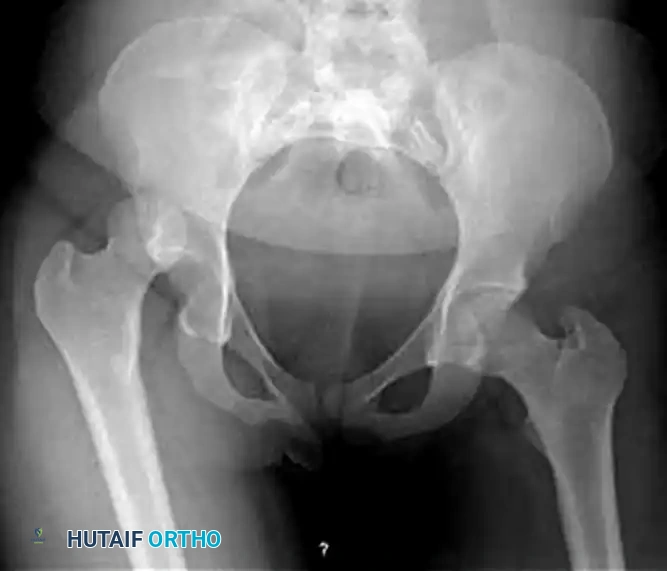

Standard Advanced Trauma Life Support (ATLS) protocols dictate an anteroposterior (AP) radiograph of the pelvis. This single view is usually sufficient to diagnose a posterior dislocation and identify gross concomitant fractures of the femoral head, neck, or acetabulum.

FIGURE 55-52 C: Preoperative AP radiograph demonstrating a posterior hip dislocation with a concomitant femoral head fracture.